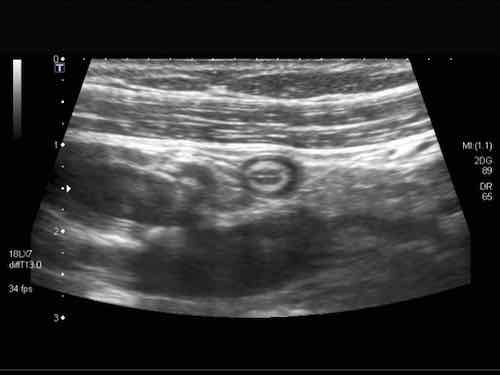

Ruột non bình thường có thể dễ dàng quan sát bằng siêu âm và được nhận biết qua nhu động ruột liên tục và rõ ràng, ngay cả khi lòng ruột trống rỗng.

Lưu ý nhiều vùng giảm âm nhỏ hình tròn với đường viền tăng âm trong lớp dưới niêm mạc sáng.

These represent normal 0.4 – 0.5 mm vessels.

Cũng lưu ý đường tăng âm mỏng bên trong lớp cơ, đại diện cho mô liên kết ngăn cách lớp cơ dọc và lớp cơ vòng, chứa đám rối Auerbach.

Normal small bowel in the longitudinal plane.